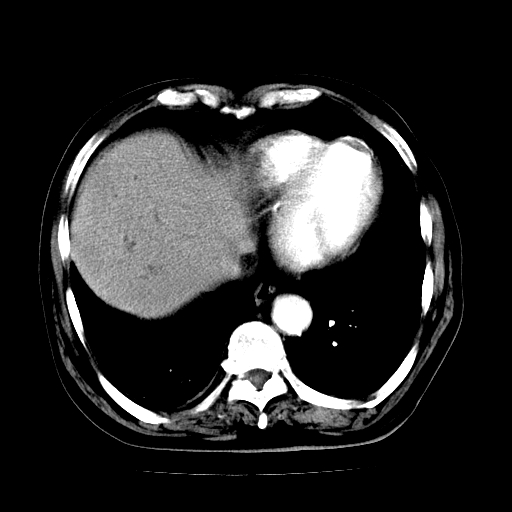

男,71岁,皮肤黄染四天。

肝内外胆管及胆总管上段扩张,考虑为梗阻所致,建议mrcp检查。

考虑胆总管癌并肝内外胆管扩张。

胰腺上端胆总管内见软组织影,强化不明显,结合临床,还是考虑低位梗阻性黄疸,胆总管癌可能性大